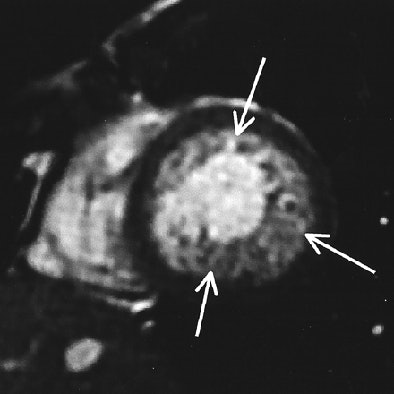

| Fig. A (above), 23-year-old woman referred to MRI with suspicion of transposition of great arteries because of prominent trabeculation of subaortic ventricle in echocardiography. Time-resolved coronal maximum-intensity-projection angiograms (B-C, below) and cine short-axis view (D, bottom). The angiograms show normal time course of enhancement of subpulmonary atrium and ventricle and pulmonary arteries (A); and enhancement of pulmonary veins, subaortic atrium, ventricle, and aorta (B). Note decreasing enhancement of subpulmonary ventricle from A to C, indicating absence of relevant left-to-right shunt flow. This patient suffered from noncompaction myocardium, which is visualized on time-resolved MR angiography (C) (arrow) and is shown on cine short-axis view (D) (arrows). Republished with permission of the American Roentgen Ray Society from AJR 2006; 187:1107-1114. |